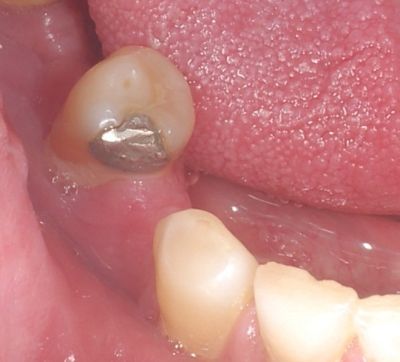

Autor zdjęcia/źródło: Rycina 1. Wypełnienie amalgamatowe zęba drugiego przedtrzonowego w żuchwie (fot. W. Bereziewicz)

Duża wytrzymałość mechaniczna i stosunkowo mniejsza wrażliwość amalgamatów na wilgoć tłumaczy ich powszechne stosowanie jako materiał do wypełnień ubytków w zębach bocznych mlecznych i stałych.1 W piśmiennictwie podaje się, że miejscowa reakcja na rtęć stanowiącą składnik wypełnień amalgamatowych może spowodować odczyny liszajowe w jamie ustnej.2